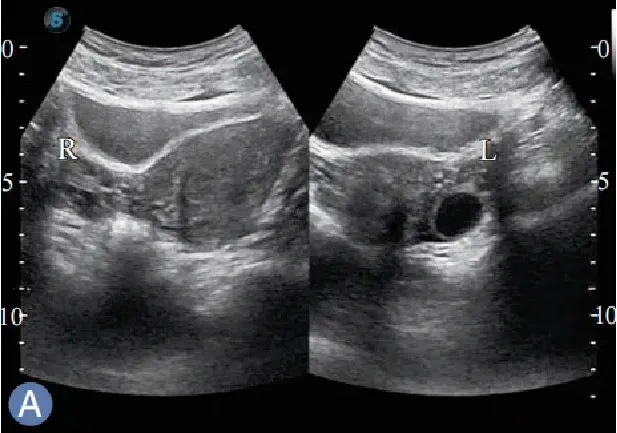

卵巢

●一对扁椭圆形性腺,分为皮质和髓质。

●位于子宫底后外侧、盆腔侧壁髂内、外动脉分叉处的下方,借卵巢固有韧带连于子官角。

卵巢斜切扫查

仰卧位,扫查右( 左)侧卵巢探头斜置于耻骨联合左(右) 上方,对腹壁适当加压,使声束朝向右( 左)后方,以膀胱做透声窗,显示右(左)侧卵巢。